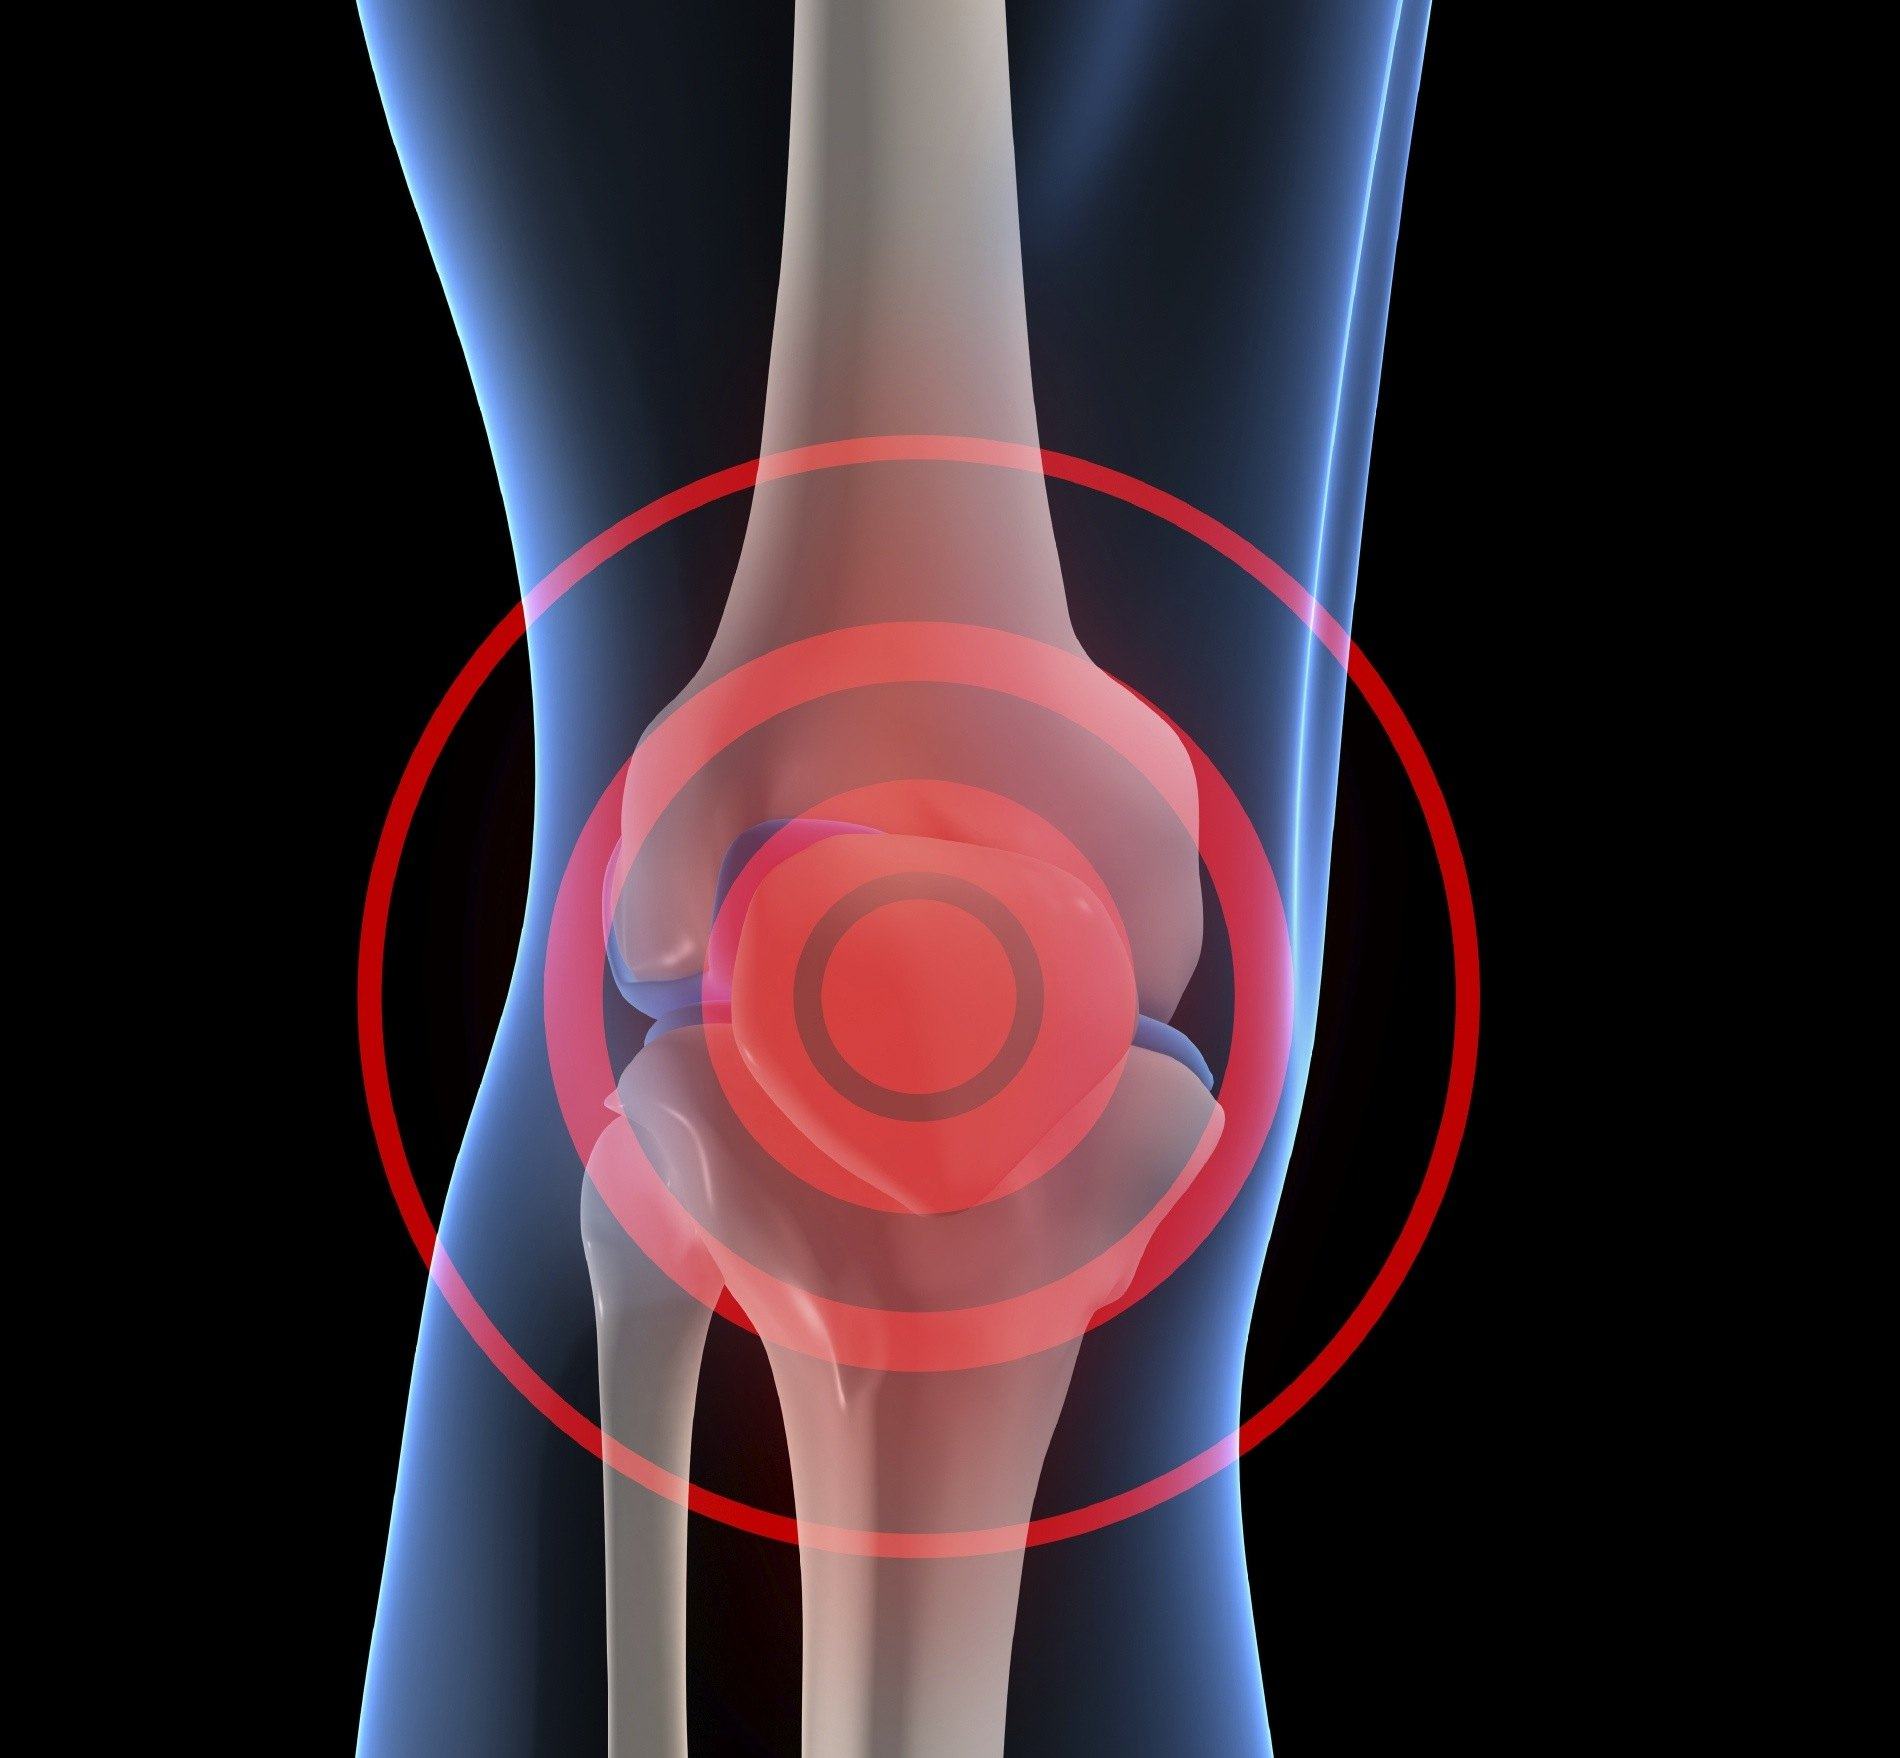

Cambios en la movilidad de las articulaciones, en la facilidad con la que hacemos las actividades diarias o aumentos del dolor articular generan una de pregunta común de nuestros oyentes: ¿cuando es necesario colocar una prótesis?

En una cirugía un traumatólogo puede sustituir de forma parcial o total las superficies de una articulación con el objetivo de restaurar la movilidad y mejorar la calidad de vida.

Aunque se espera que sean los ancianos quienes la ameriten por afecciones del cartílago articular como la osteoartrosis o la alteración de la cantidad de nutrientes que llegan al hueso a través de la sangre como sucede en la necrosis avascular existen personas muy jóvenes que por enfermedades congénitas o por accidentes de tránsito son susceptibles para realizarse el reemplazo.

Una prótesis no es para toda la vida, ya que la limitación principal de un remplazo es el desgaste del implante, que en el mejor de los casos dura unos 20 años, por lo que su uso en los jóvenes no es la primera opción, salvo por supuesto, en los casos en que lo amerite.

En Venezuela y el mundo el remplazo articular por excelencia es la rodilla y en 2do lugar la cadera ocupando alrededor del 85% de todos los reemplazos.

Por fortuna, muchos de los pacientes que acuden a consulta tienen trastornos articulares que detectados tempranamente no ameritan reemplazo como: las lesiones meniscales, hernias discales, lesión de ligamentos cruzados, rupturas del manguito rotador, condiciones previsibles si realizamos ejercicio y comemos balanceadamente como medida para mantener nuestra salud muscular y articular.